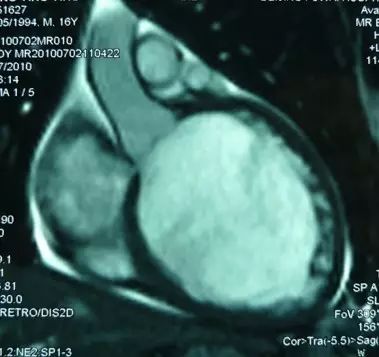

MRI

►左室腔明显扩大,室间隔及左室壁普遍变薄,各节段运动减弱

►心肌延迟强化未见明显异常

►考虑符合扩心病、心衰